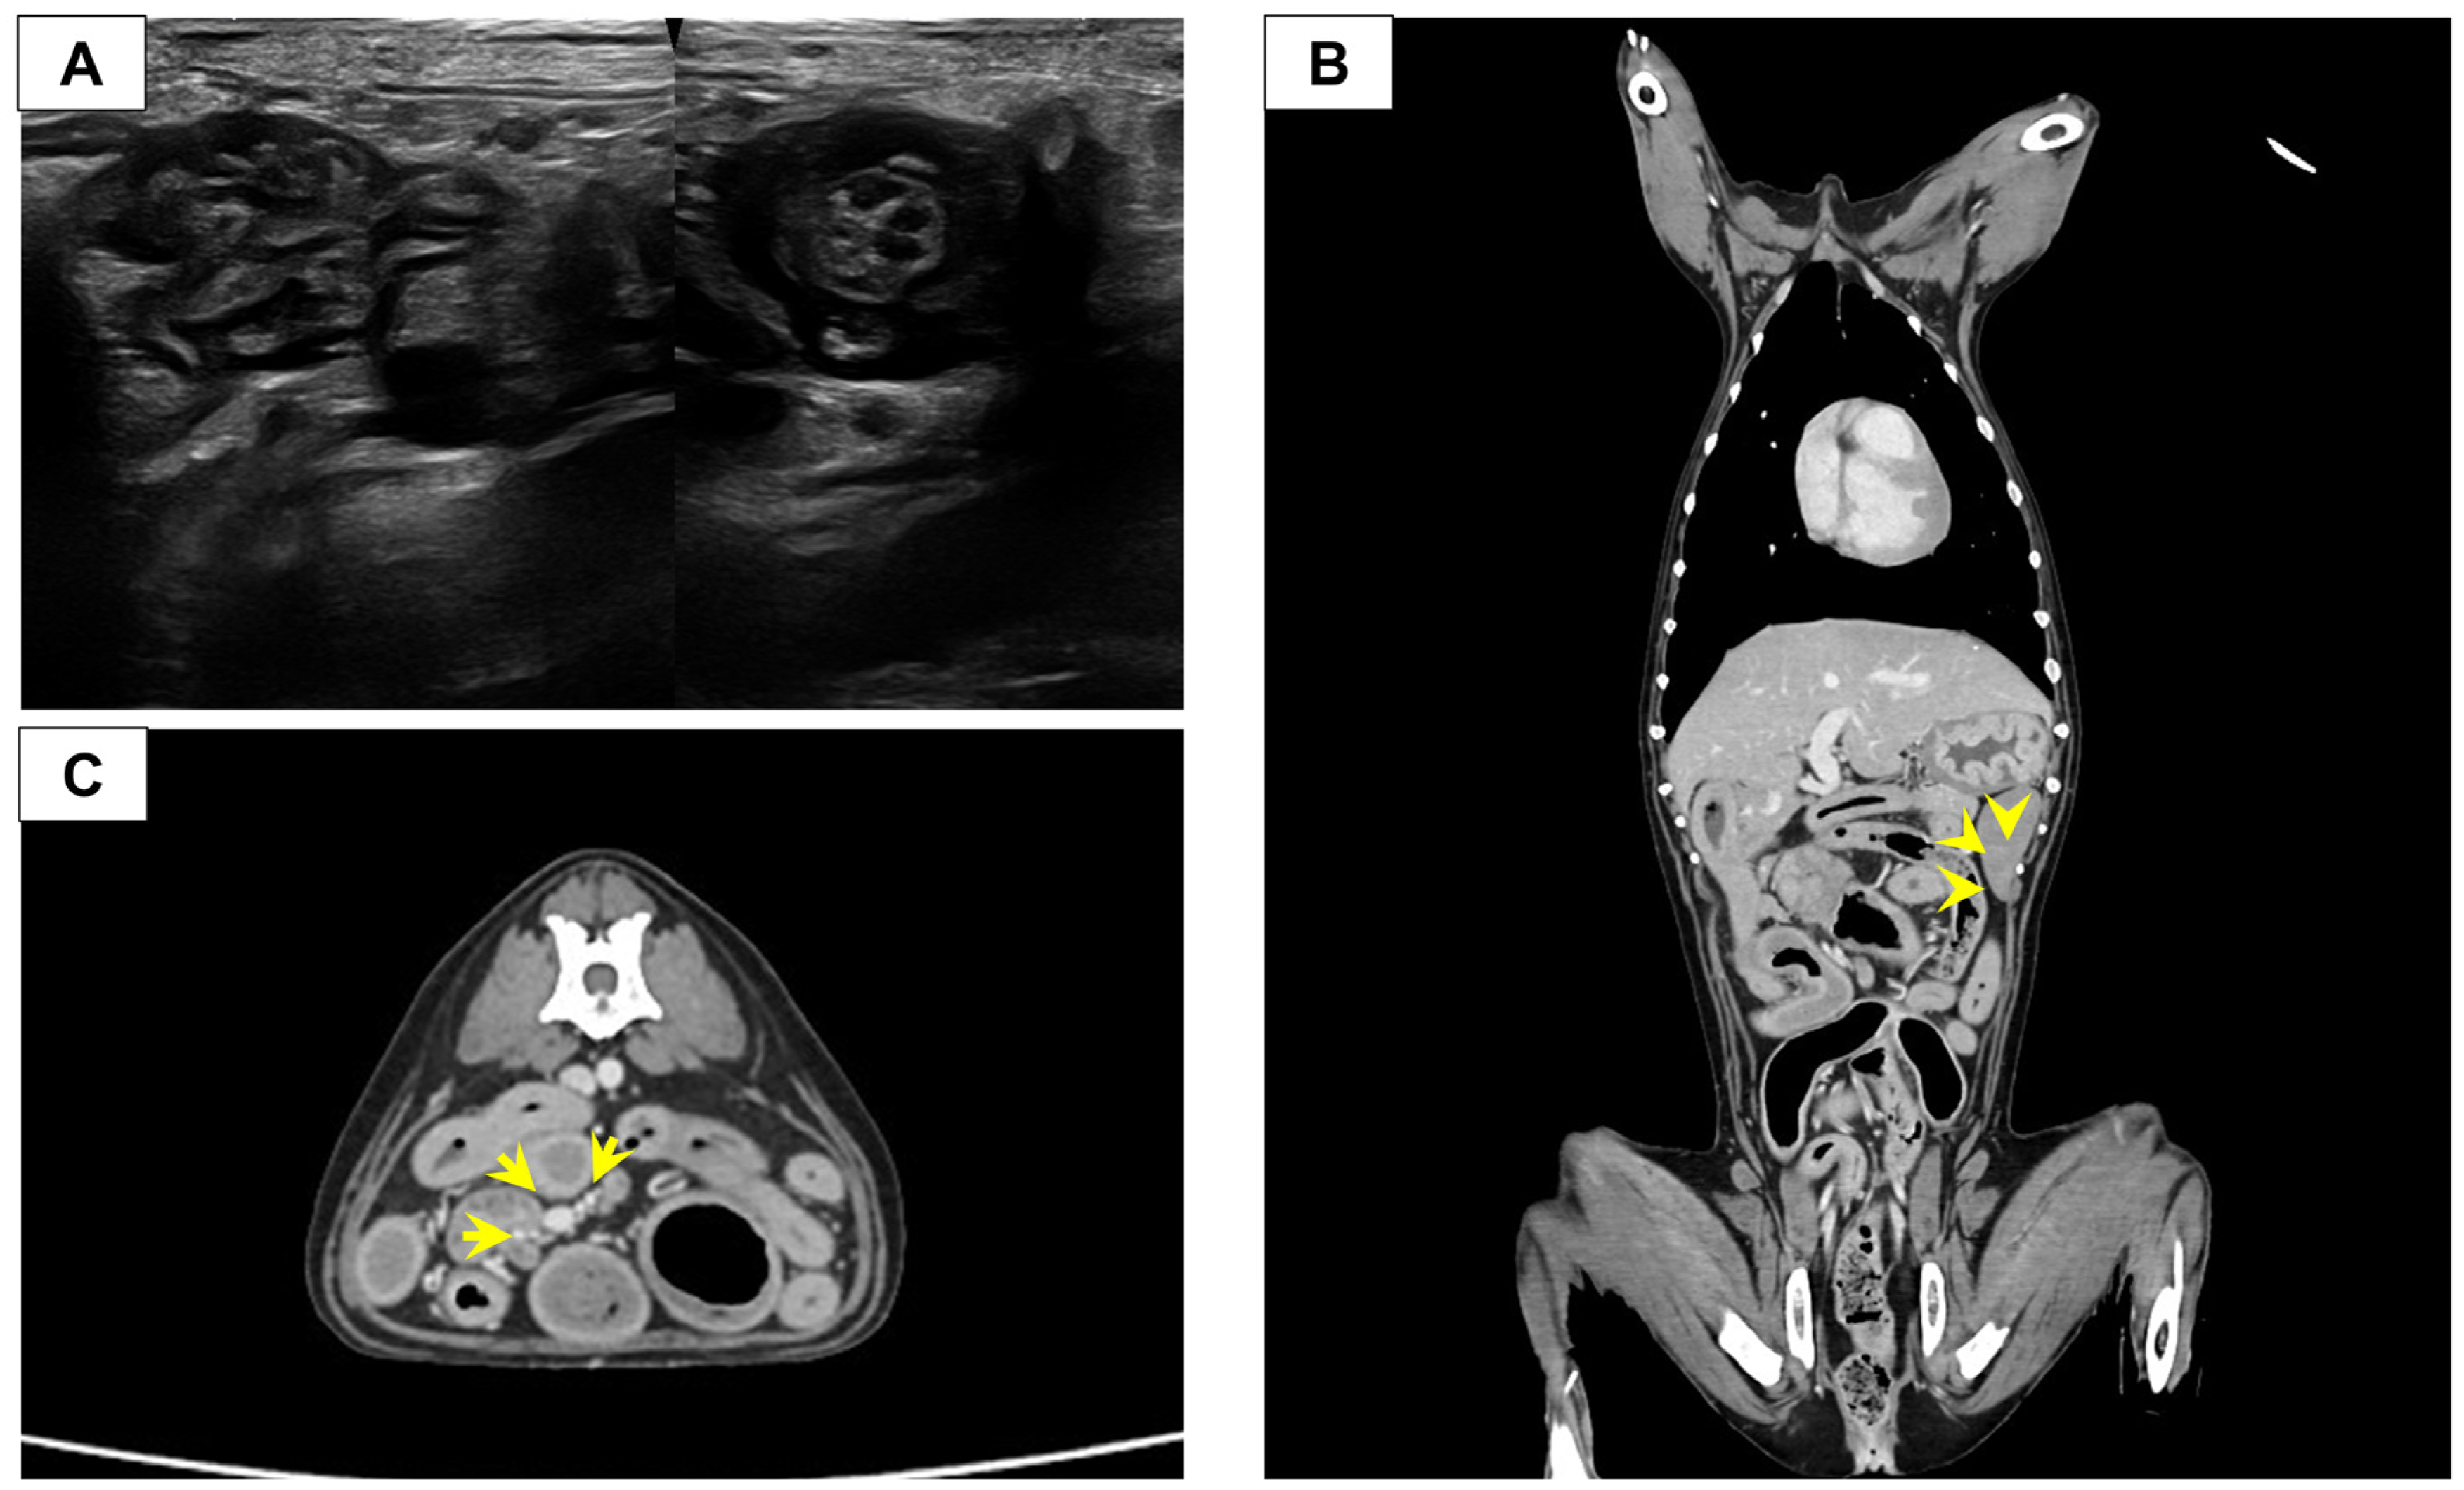

Abdominal radiographs obtained at presentation demonstrated segmental dilation of the small intestine, raising concern for a partial mechanical obstruction. Abdominal ultrasonography identified a localized lesion at the ileocolic junction (ICJ). Focal thickening of the ileal muscularis layer adjacent to the ICJ was noted, accompanied by an abnormal overlapping configuration (Figure 1A), raising suspicion for partial intussusception or an intestinal stricture. The intestinal wall layering was preserved, and no ultrasonographic findings were indicative of complete mechanical obstruction at the time of evaluation. Moderate enlargement of the regional lymph nodes was also noted, with heterogeneous hypoechoic parenchyma. The differential diagnoses considered included benign inflammatory disorders, such as chronic enteropathy or lipogranulomatous lymphangitis, as well as partial intussusception and intestinal neoplasia. Because the ultrasonographic findings were inconclusive and mechanical obstruction could not be ruled out, advanced diagnostic imaging was pursued for detailed characterization of the lesion and evaluation for possible malignancy.

Subsequent CT imaging confirmed a severe, circumferential, and symmetric wall thickening of the distal ileum (maximum thickness 10 mm, length approximately 23 mm). This severe pathology resulted in a non-discernible intestinal lumen at the lesion level, leading to the loss of luminal patency (Figure 1B). Proximal to the stricture, severe small intestinal dilation was confirmed (maximum diameter: 27.4 mm, small intestine (SI) to L5 vertebral body ratio = 3.3) with intraluminal high-attenuating material (small bowel feces sign), suggesting complete mechanical obstruction. Regional lymphadenopathy was also apparent; the jejunal lymph node adjacent to the ICJ lesion was significantly enlarged (20.9 × 12.5 × 9.5 mm) and exhibited heterogeneous contrast enhancement on CT (Figure 1C). Bilateral adrenal enlargement was also noted, measuring a maximum diameter of 7.6 mm at the cranial pole, which was consistent with the patient’s history of hyperadrenocorticism. Given the presence of complete mechanical obstruction and the persistent inability to exclude malignancy based on imaging findings, surgical intervention was required for both immediate alleviation and definitive histopathological diagnosis.

Figure 1. Diagnostic imaging (Computed Tomography (CT) and Ultrasonography) illustrating the ileocolic junction (ICJ) lesion and key associated diagnostic findings at the ICJ. (A) Sagittal (left) and Transverse (right) ultrasonographic image of the ICJ. (B) Coronal CT image (Delayed phase) of the ICJ. The image reveals severe, circumferential wall thickening (maximum 10 mm) resulting in non-discernible luminal patency (arrowhead). (C) Transverse CT image (Delayed phase) of the Jejunal lymph node (LN) adjacent to the lesion. The lymph node demonstrates significant enlargement (L × H × W = 20.9 × 12.5 × 9.5 mm), accompanied by thickening and heterogeneous contrast enhancement (arrow).